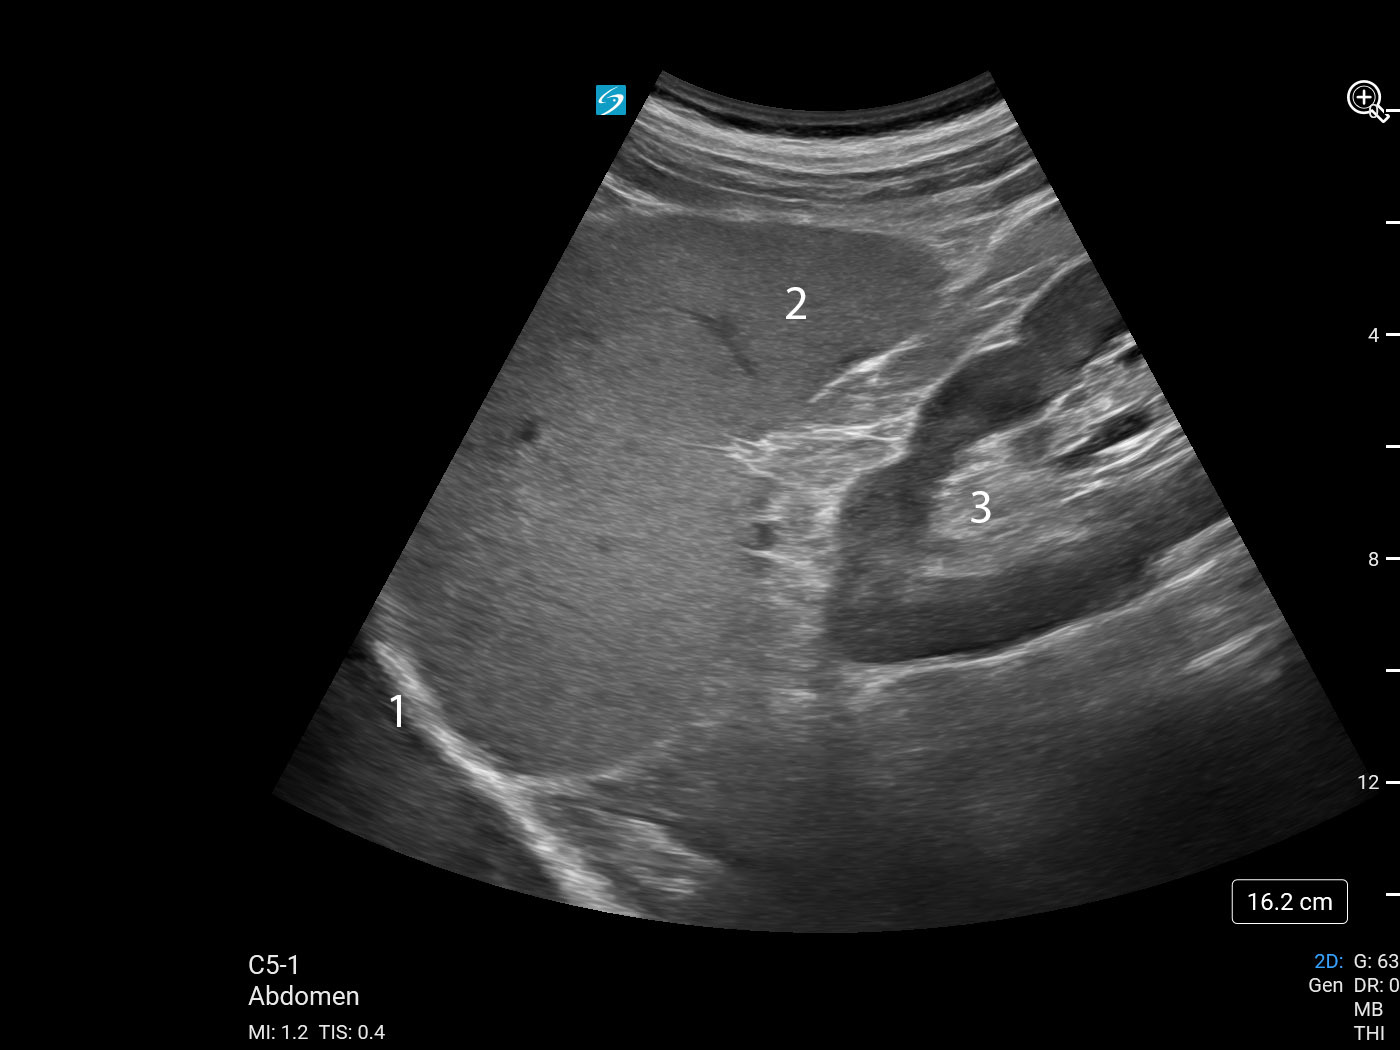

左上腹部 (LUQ) 脾臓・左腎臓イメージ

横隔膜

胸膜腔

脾臓

腎臓